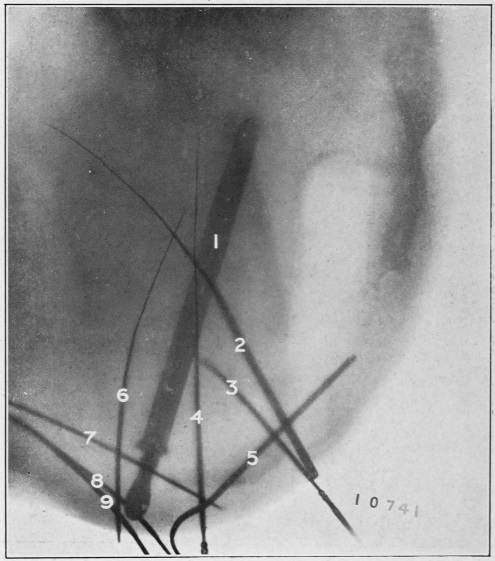

Nine Radiograph Illustrations Showing Mucus Channels and Cavities200

CHAPTER XXV.

Chronic Mucous Proctitis and Sigmoiditis—Usually Diagnosed as Chronic Mucous Colitis202